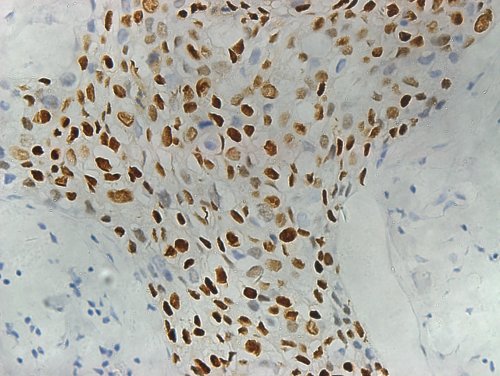

该产品孕激素受体检测试剂盒(免疫组织化学法),Progesterone Receptor Detection Kit (IHC)的主要组成成分有: 试剂A—单克隆兔抗人孕激素受体工作液、 试剂B—空白对照试剂 、 试剂C—柠檬酸盐修复缓冲液 (粉剂) (具体内容详见说明书 )。 预期用途:试剂盒用于体外检测经福尔马林固定、石蜡包埋的人乳腺癌组织切片中孕激素受体。